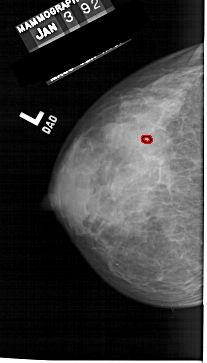

A_1257_1.LEFT_MLO

LEFT_MLO LINES 6466 PIXELS_PER_LINE 3511 BITS_PER_PIXEL 12 RESOLUTION 43.5 OVERLAY

FILE: A_1257_1.LEFT_MLO.OVERLAY

TOTAL_ABNORMALITIES 1

ABNORMALITY 1

LESION_TYPE CALCIFICATION TYPE PLEOMORPHIC DISTRIBUTION CLUSTERED

ASSESSMENT 4

SUBTLETY 1

PATHOLOGY MALIGNANT

TOTAL_OUTLINES 1

BOUNDARY